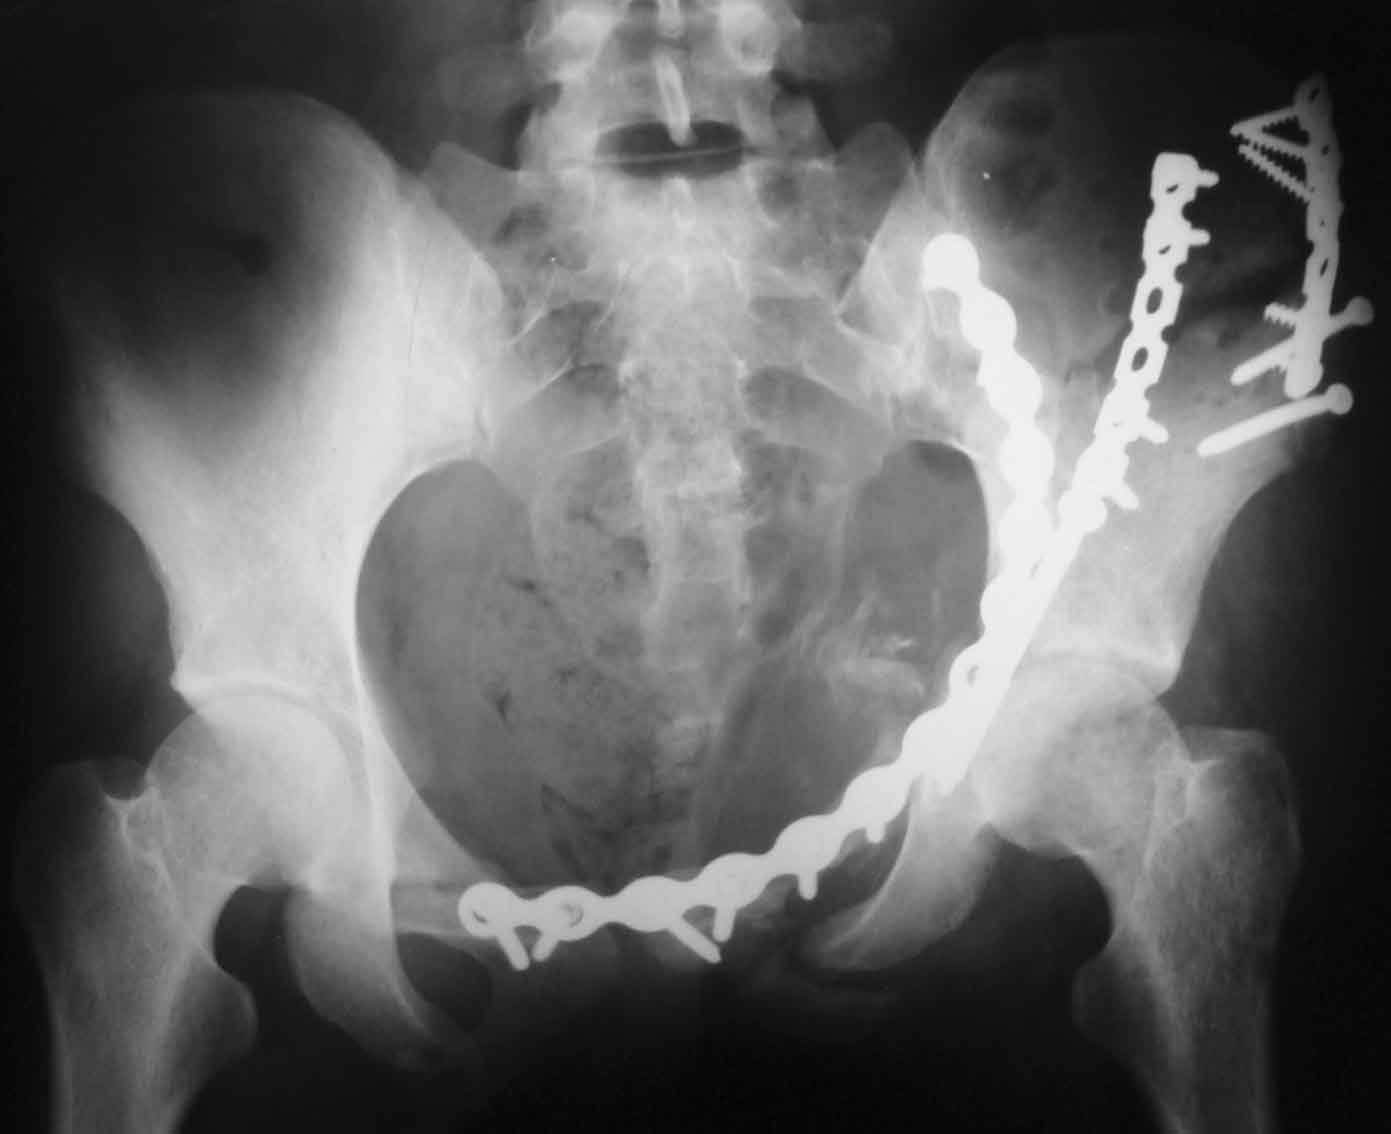

Рентгенограммы после операции

inlet